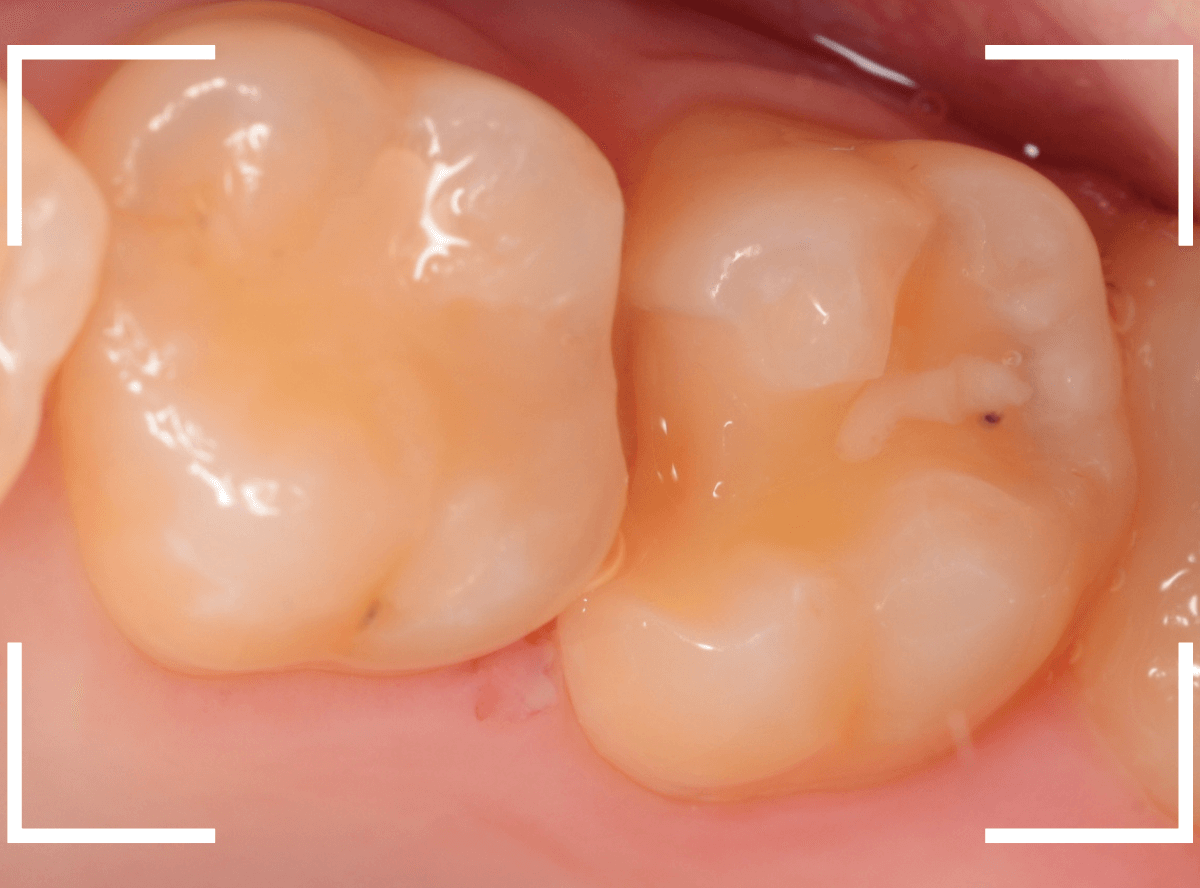

Case.27 乳歯をセラミック・インレー

昔に治療したセラミック・インレーが破折した患者さんのケースです。

破折している部分はわずかですが、セラミックの内面~となりの歯のレジンの中まで虫歯が見られます。

この歯は後続の永久歯のない、乳歯になります。

今後、どの程度保存できるか何とも言えませんが、幸い歯の揺れもなくしっかりしているので、短期間で抜歯が必要になったする事はないとの判断で、セラミック・インレーを除去して再治療する事になりました。

虫歯と歯のトリミング処置したところです。

奥歯をレジンでつめ直し、手前の乳歯はE-max・インレーで再製する事になりました。

模型上で精密に製作します。

治療後の状態です。

見た目の違和感なく、仕上げられたかと思います。

いつもしているお話なりますが、特にこの歯はできるだけ長持ちさせるために、定期メンテナンスに忘れずに来ていただく事をお話しして治療終了になりました。